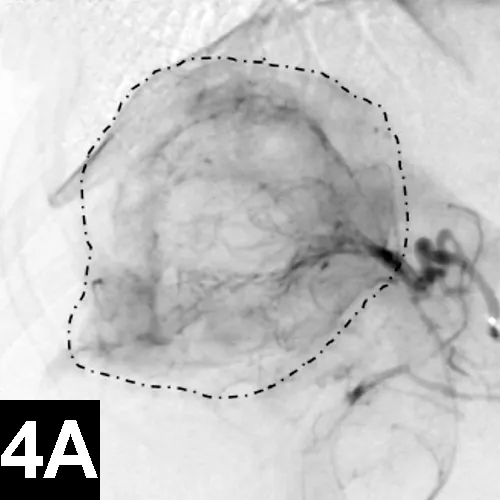

Clinical improvement can be achieved in 75% to 90% of animals treated with self-expanding metallic stents (Figure 1), an IR procedure.4 Immediate adverse events were mostly minor; however, a perioperative mortality rate of about 10% was reported. Longer-term adverse events included shortening of the stent, fracturing of the stent, progressive tracheal collapse, and excessive granulation tissue.

Figure 1A: Serial lateral fluoroscopic images of a dog with tracheal collapse.

A positive pressure ventilation demonstrates maximal dilation of the trachea. A marker catheter in the esophagus is used to account for radiographic magnification.